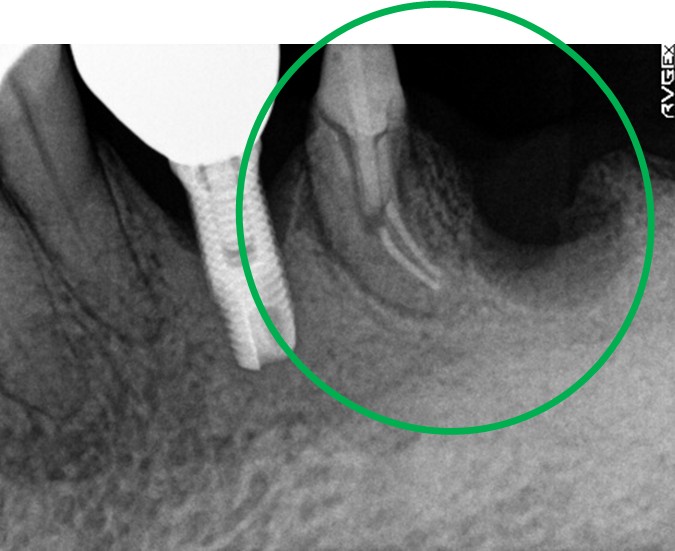

女性 Sさん 50代 (オールセラミック冠)

主訴

左上の差し歯がとれたままになっている。

治療内容

レントゲンを撮り詳しく診てみると、歯根が破折して保存することができず、抜歯する必要があることがわかりました。抜歯後、オールセラミックブリッジで補綴(欠損した部分を人工物で補う)しました。ブリッジの支台になっている後方の歯は、根尖性歯周炎(根の先端で問題を起こしている)でしたので、根管治療をしています。

所感

抜歯後、欠損部分を補う方法には、1本だけの部分入れ歯、ブリッジ、インプラントの3つの方法があります。この患者さんは、ブリッジを選択されました。メタルフリーの治療を希望されましたので、土台をファイバーコアにし、オールセラミックのブリッジをかぶせました。患者さんは、お口の中の金属を徐々に減らしていきたいということです。体全体の健康のことを考えると正しいことです。

オールセラミック冠(失活歯)1本:¥104,500(税込)

オールセラミック冠(生活歯)1本:¥93,500(税込)

ポンティック1本:¥93,500(税込)

合計:¥291,500(税込)

Before

After